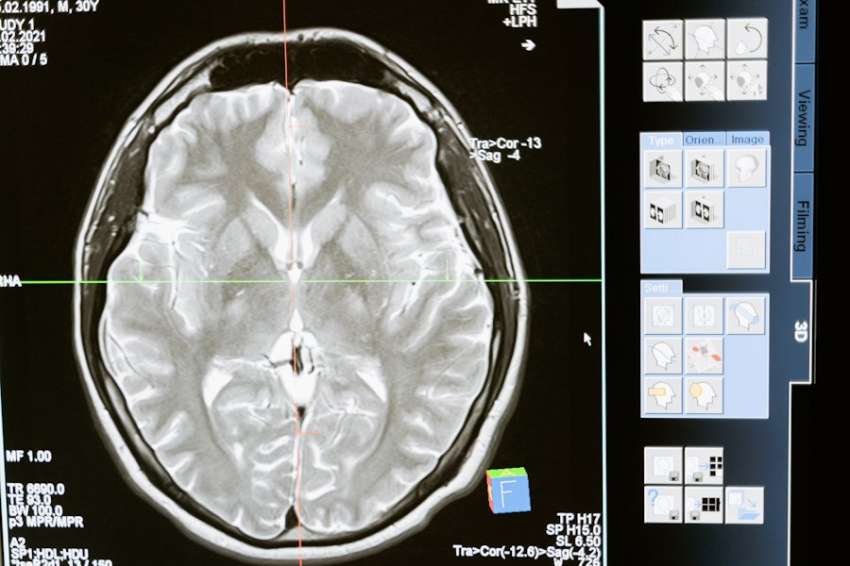

Китайские ученые выяснили: бессмертие мозга возможно

Группой китайских исследователей совершен настоящий прорыв в крионике. Им удалось разработать методику заморозки и оттаивания тканей головного мозга, не дающей повреждения клеток.

Как сообщает публикация в журнале Cell Reports Methods, до сих пор аксиомой было, что алгоритм замораживания и оттаивания неизбежно дает повреждение и разрушение ткани мозга. Китайские эксперты применили обработку этих тканей особым набором химических соединений.

Они назвали эту чудодейственную смесь MEDY, это аббревиатура из названий составных частей микста: этиленгликоль, метилцеллюлоза, диметилсульфоксид и Y27632 — ингибитор Rho-киназы.

В ряде экспериментов ученые выяснили, что MEDY ограждает органоиды головного мозга от клеточной гибели и содействует экспрессии генов, которые принимают участие в развитии нейронов и синаптических функциях.

Мозговые ткани обрабатывали таким раствором и замораживали жидким азотом и затем подвергали разморозке. После полутора лет хранения оказалось, что ткани почти не отличались от обычных, сохранили функциональность и способность к росту.

Ученые считают метод крайне перспективным. Таким образом функциональность мозга можно сохранять на долгое время, практически приближая человека к частичному бессмертию.